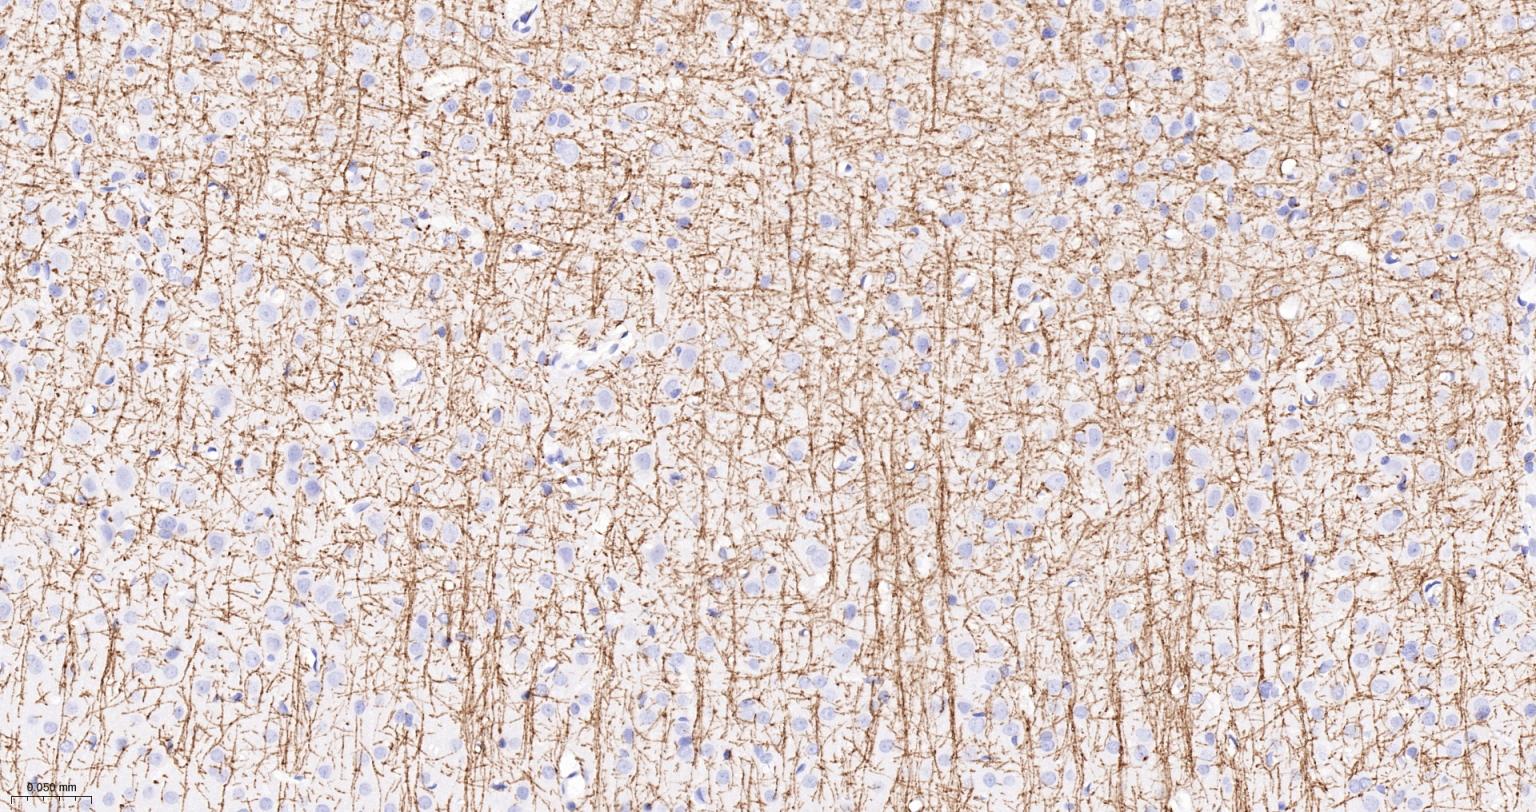

8. 显色

用吸水纸吸去玻片上多余的液体,在每张切片上滴加约50 μL新配制的DAB工作液(试剂7:试剂8:PBS=1:1:18),作用3-5 min。显微镜下观察结果,达到合适的显色强度后,用蒸馏水冲洗切片以终止反应,用蒸馏水冲洗5 min,重复3次。

| IHC-P | Human, Mouse, Rat | 1:200-1000 | |